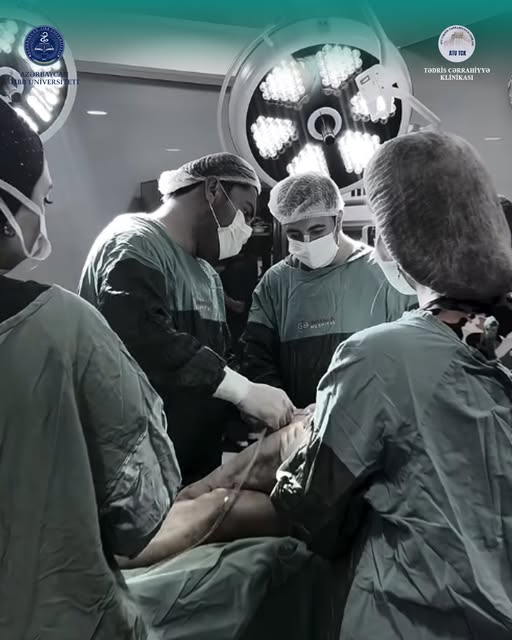

Ayağında geniş toxuma zədələnməsi yaranan pasiyentdə mürəkkəb rekonstruktiv əməliyyat uğurla icra olunub

16.06.2026 | 14:09